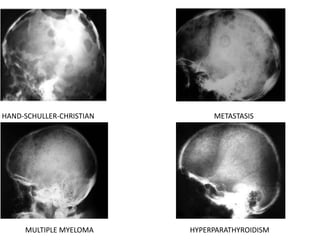

Multiple Radiolucent Defects

Children

• Craniolacunia

• Wormian Bones

• Increased Convolutional Markings

• Histiocytosis

• Metastasis – neuroblastoma, leukemia, Ewing’s Sarcoma

Adults

• Multiple Myeloma

• Metastasis

• Hyperparathyroidism

HAND-SCHULLER-CHRISTIAN METASTASIS

MULTIPLE MYELOMA HYPERPARATHYROIDISM

Malignant lesions • Primaryosteosarcoma – gross destruction of the bone with well defined margins and soft-tissue component • Metastasis • Intacranial mass lesions may present as lytic skull lesion Neurofibromatosis is a rare cause of lytic skull lesion – not due to neurofibroma, but due to mesenchymal defect. Histiocytosis X ( Eosinophilic granuloma, Letterer-Siwe disease, Hand-Schüller-Christian disease) • A single lytic lesion having sharp, non-sclerotic barder and bevelled edges is characteristic of eosinophilic granuloma. • A small bone in the center – Button sequestrum. • Other two variants have larger, multiple and punched out lesions

Multiple Radiolucent Defects Children •Craniolacunia • Wormian Bones • Increased Convolutional Markings • Histiocytosis • Metastasis – neuroblastoma, leukemia, Ewing’s Sarcoma Adults • Multiple Myeloma • Metastasis • Hyperparathyroidism